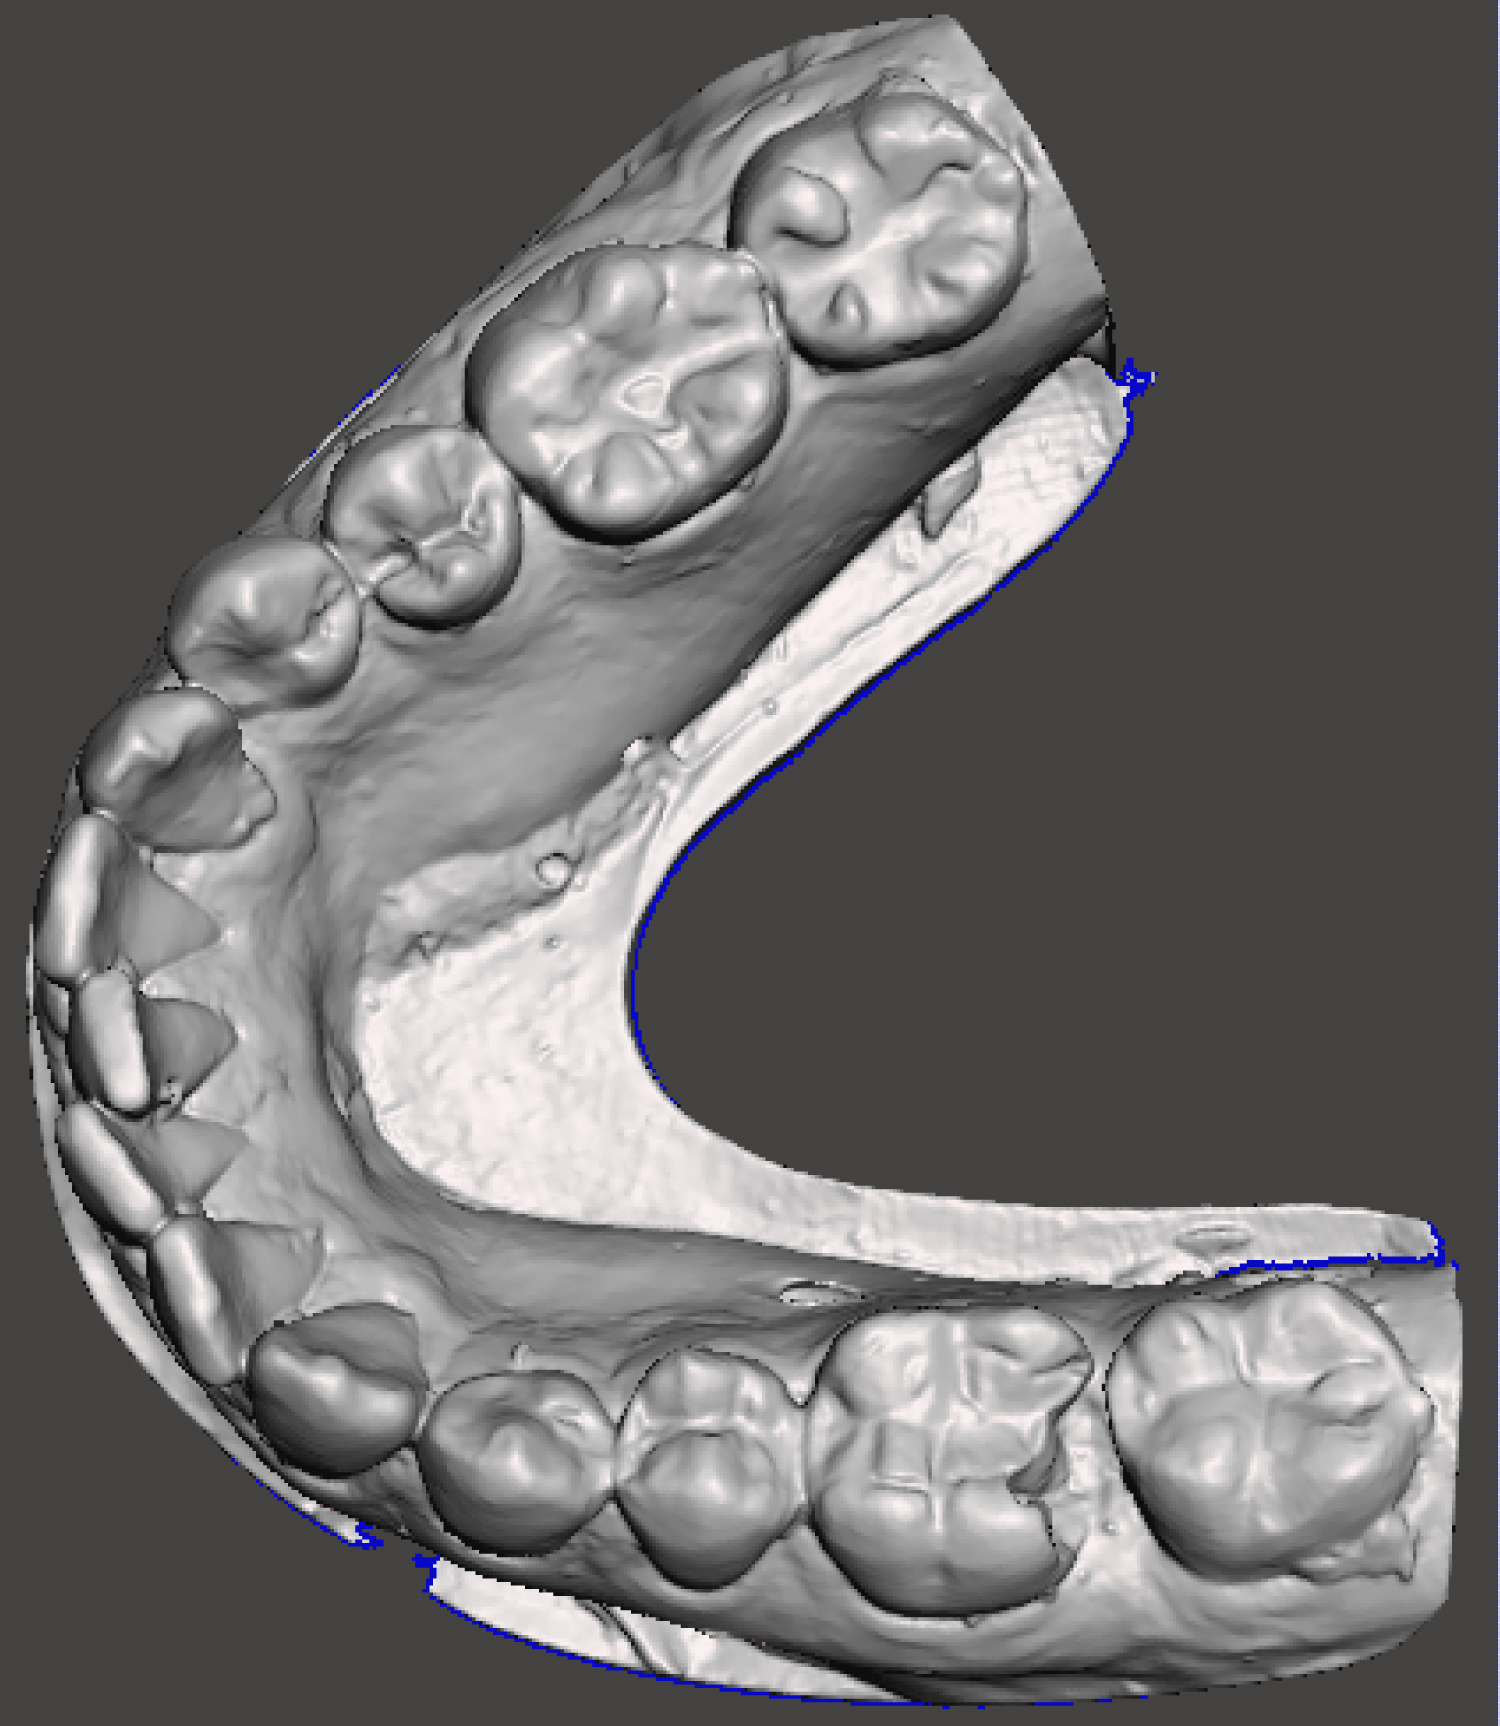

A 29-year-old female patient attended the Oral and Maxillofacial Surgery Unit of University Hospital of Maracaibo, Venezuela, presenting pain in the posterior left mandibular region. Her medical record was unremarkable. On clinical examination, the inferior left first molar (#36) presented with endodontic treatment which had been performed in two previous opportunities due to the persistence of associated pain on vertical and transversal percussion. A panoramic X-ray was requested, and the endodontic treatment with a partially fractured crown was observed in the aforementioned tooth, with no radiolucent images associated (Figure 1). Due to these findings, the final diagnosis of cracked tooth syndrome was decided and thus, the treatment plan chosen was to extract the tooth and place an implant using a surgical guide in the same surgery along with guided bone regeneration. The patient's mandibular cast was scanned using an extraoral scanner (Ceramill Map 300, Amann Girrbach, Austria) (Figure 2) and the STL file was obtained and edited in order to eliminate the crown of the tooth using MeshMixer program (Autodesk, Canada) (Figure 3). The edited denture scan was aligned to the mandibular CBCT scan of the patient in Blue Sky Plan (Blue Sky Bio, USA) to allow for prosthetically driven implant planning. Implant placement simulation was carried out in the software aiming for the site with the most surrounding bone while being prosthetically acceptable (Figure 4) and a surgical guide was designed and printed in a desktop 3D printer (AnyCubic Photon, China) (Figure 5 and Figure 6). Under moderate sedation and local anesthesia, the molar was a traumatically extracted, the surgical guide was held in position (Figure 7) and a 4.0 × 13 mm IS II active implant (NeoBiotech, Korea) was placed using the NeoBiotech Naviguide system. Subsequently, the alveolar gaps were filled using cortico-cancellous bone allograft (Ossogen, Lattice Biologics, USA) (Figure 8) and two Platelet-Rich Fibrin (PRF) membranes made using the protocol described by Choukroun [6] (Figure 9). Simple sutures using 3-0 polyglactin 910 (Vicryl, Ethicon, USA) were used for closure.

Figure 2: Unedited digital cast of the patient. View Figure 2

Figure 3: Digital cast of the patient after editing out the crown of the tooth to be extracted. View Figure 3